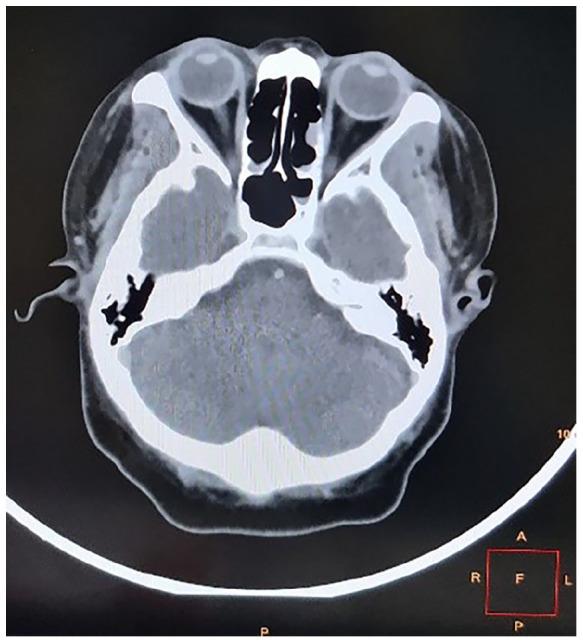

Although echinococcosis is a common parasitic disease endemic to Africa, ocular echinococcosis is rare. We present a case of intraocular echinococcosis in a HIV-infected patient. A 38-year-old South African HIV-infected woman presented to a district-level hospital in Kwa-Zulu Natal on 10 March 2020. Her main presenting complaint was that of progressive, painless, bilateral visual loss. A B-ultrasonography scan revealed tractional retinal detachment on the right eye, while the left eye had tractional bands with a 'double-walled' cystic cavity causing retinal traction. A systemic work-up revealed a positive Echinococcus ELISA IgG with a value of 1.3, eosinophilia of 5.70% (0.41 × 10), and elevated C-reactive protein and erythrocyte sedimentation rate of 47 mg/L and 93 mm/hr, respectively. Based on the above clinical, biochemical and ultrasonographical evidence, a diagnosis of ocular echinococcosis was made. Our differential diagnosis includes toxic optic neuropathy, Jarisch-Herxheimer-like reaction secondary to immune reconstitution and necrotizing herpetic retinitis. She was initiated on topical and intravitreal steroids which led to decreased intraocular inflammation and dry maculae. Five months after presentation, her visual acuity remained unchanged with no light perception in both eyes. We conclude that ocular echinococcosis, although rare, can lead to severe visual impairment as there are no known definite treatment modalities for intraocular hydatid disease. Reports on co-infections with HIV and are limited with a potential scope for research.

尽管棘球蚴病是非洲常见的地方性寄生虫病,但眼部棘球蚴病却很罕见。我们报告一例HIV感染患者的眼内棘球蚴病病例。一名38岁的南非HIV感染女性于2020年3月10日前往夸祖鲁-纳塔尔省的一家区级医院就诊。她的主要主诉是进行性、无痛性双侧视力丧失。B超扫描显示右眼有牵拉性视网膜脱离,而左眼有牵拉带及一个导致视网膜牵拉的“双壁”囊腔。全身检查显示棘球蚴酶联免疫吸附试验IgG阳性,值为1.3,嗜酸性粒细胞增多为5.70%(0.41×10),C反应蛋白和红细胞沉降率分别升高至47mg/L和93mm/hr。基于上述临床、生化和超声证据,诊断为眼内棘球蚴病。我们的鉴别诊断包括中毒性视神经病变、免疫重建继发的类赫氏反应和坏死性疱疹性视网膜炎。给予她局部及玻璃体内注射类固醇药物,这导致眼内炎症减轻及黄斑干燥。就诊五个月后,她的视力仍未改变,双眼均无光感。我们得出结论,尽管眼内棘球蚴病罕见,但由于目前尚无已知的确切治疗眼内包虫病的方法,它可导致严重的视力损害。关于HIV合并感染及[此处原文缺失相关内容]的报道有限,有潜在的研究空间。